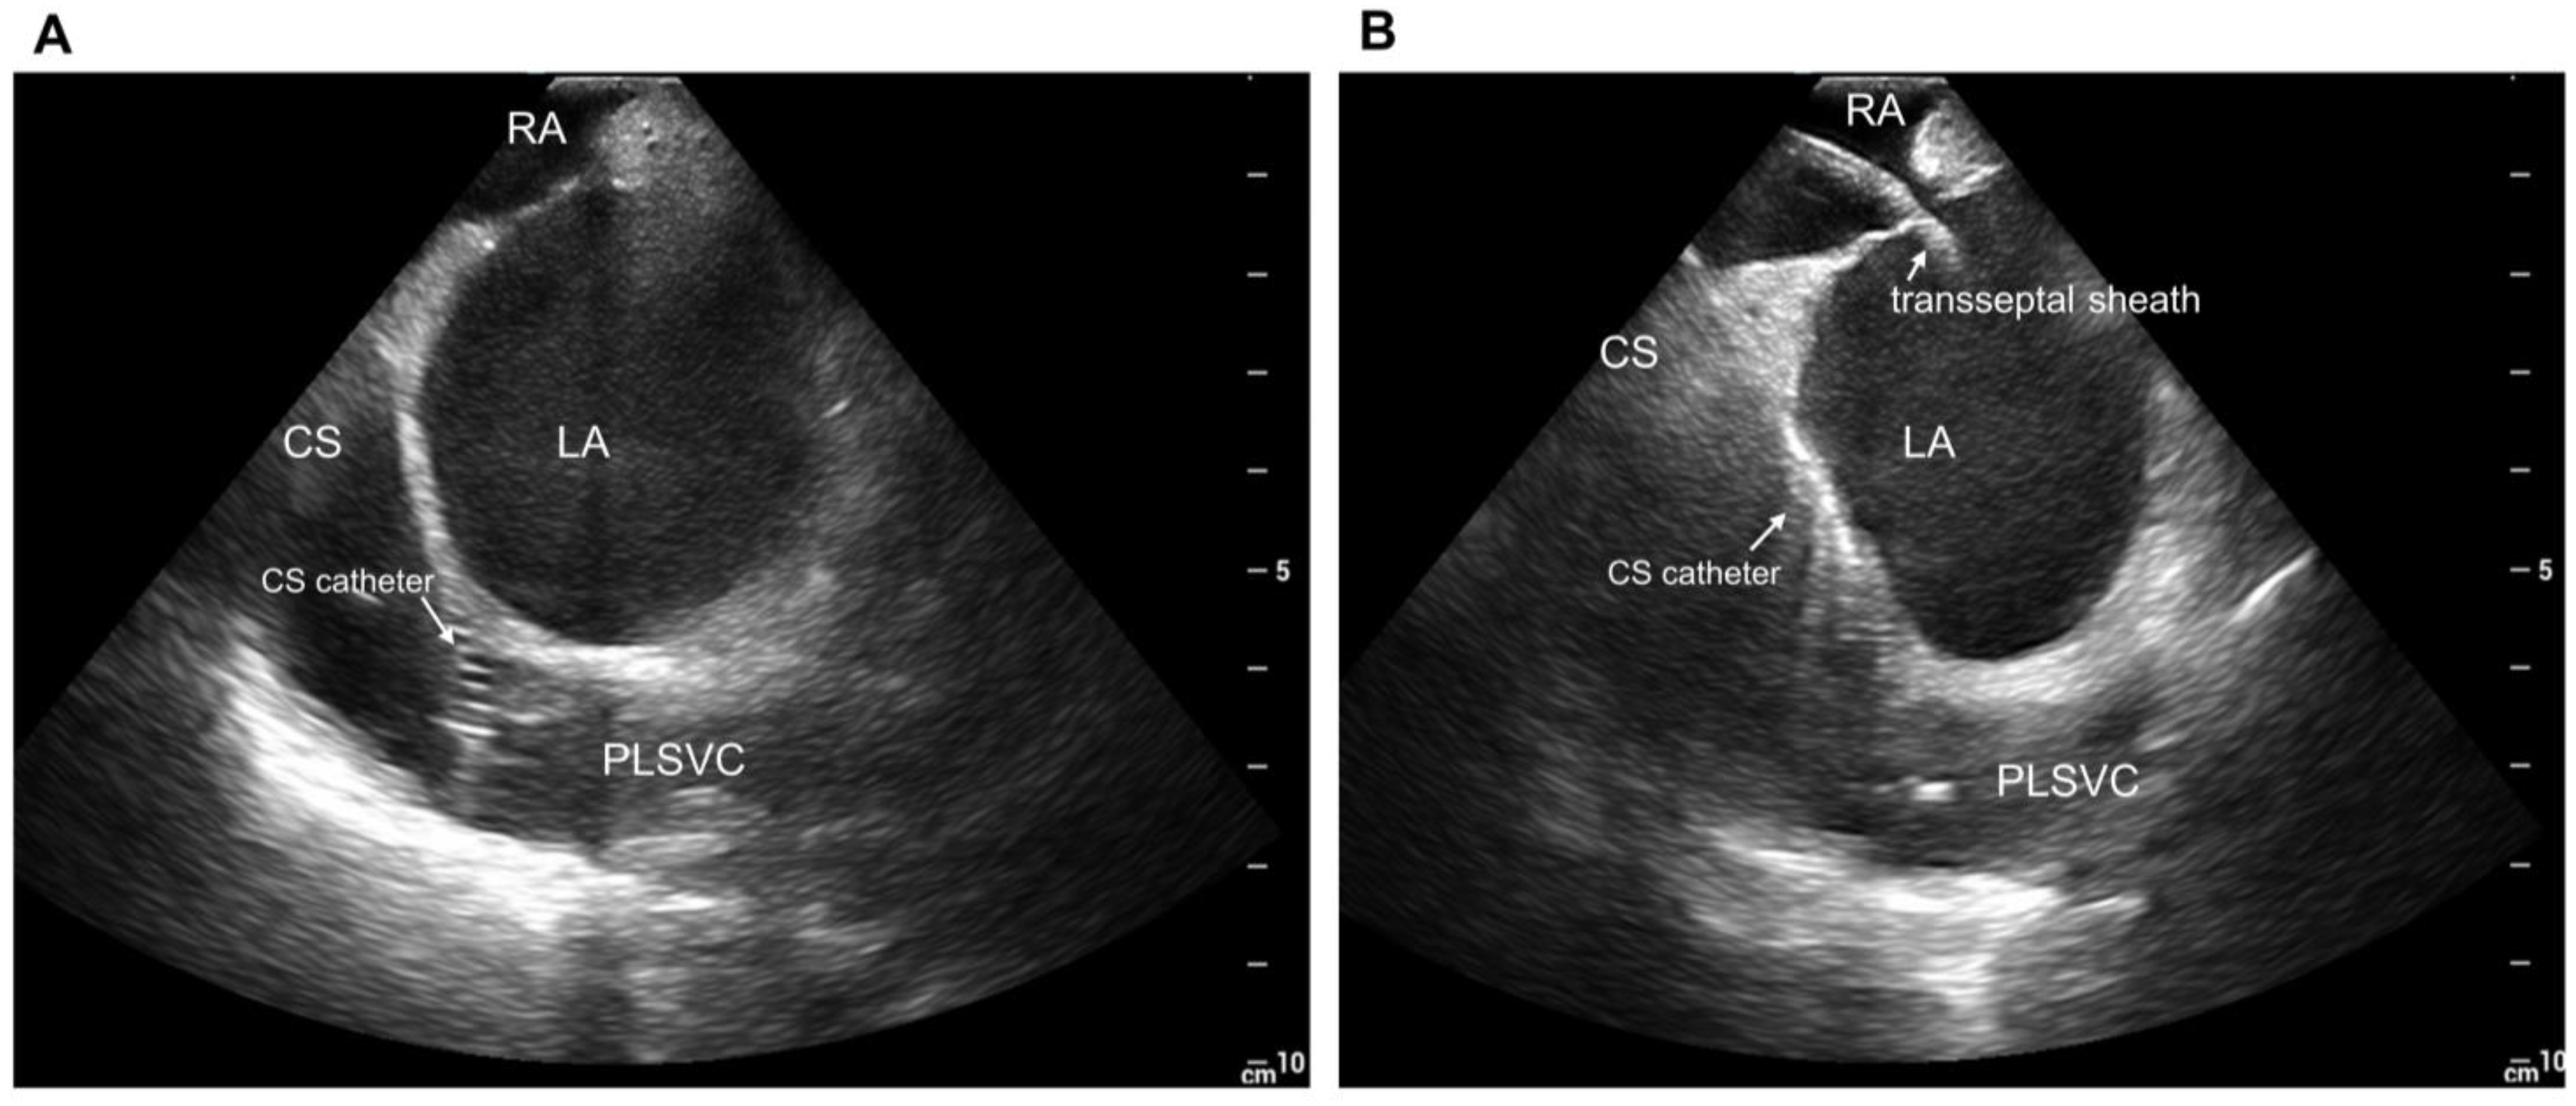

3.3. Localization of Triggers and Electrical Isolation of Persistent Left Superior Vena Cava